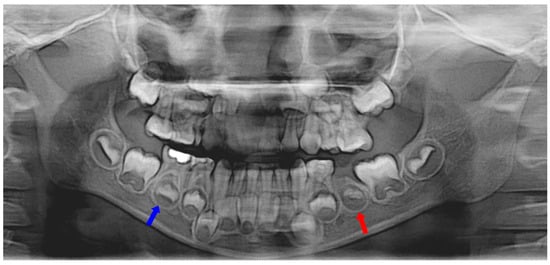

Two months after extraction, most of the extruded material was resorbed, but there was a small amount left near the successive tooth germ (Figure 1b). Eleven months after extraction, radiological examination showed the underdevelopment of permanent successive tooth germ compared to the opposite side (Figure 1c and Figure 2).

Figure 2.

Eleven months after tooth extraction. Panoramic radiograph. The underdevelopment of the left mandibular second premolar tooth germ (red arrow) was observed compared with the opposite one (blue arrow).

A band and loop space maintainer was delivered after the eruption of the left mandibular first molar. Three years after the extraction, the development of the successive permanent tooth was observed (Figure 1d). Four years post-extraction, the successive tooth was in the pre-eruptive phase, with continuous growth and pre-eruptive movement in the alveolar bone, similar to those in the opposite tooth (Figure 3).